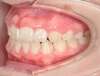

Cas 4 : Description

Chevauchement sévère. Traitement multibague sans extraction.

Avant

Après